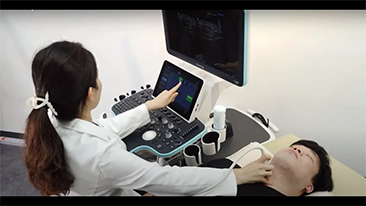

As solu??es de imagem geral Mindray Resona ajudam mĂŠdicos a obter resultados mais precisos e eficientes de diagnĂłstico e tratamento por meio de sondas de aplica??o de subdivis?es abrangentes e ferramentas eficientes de aplica??o clĂnica.

Produtos para imagem geral